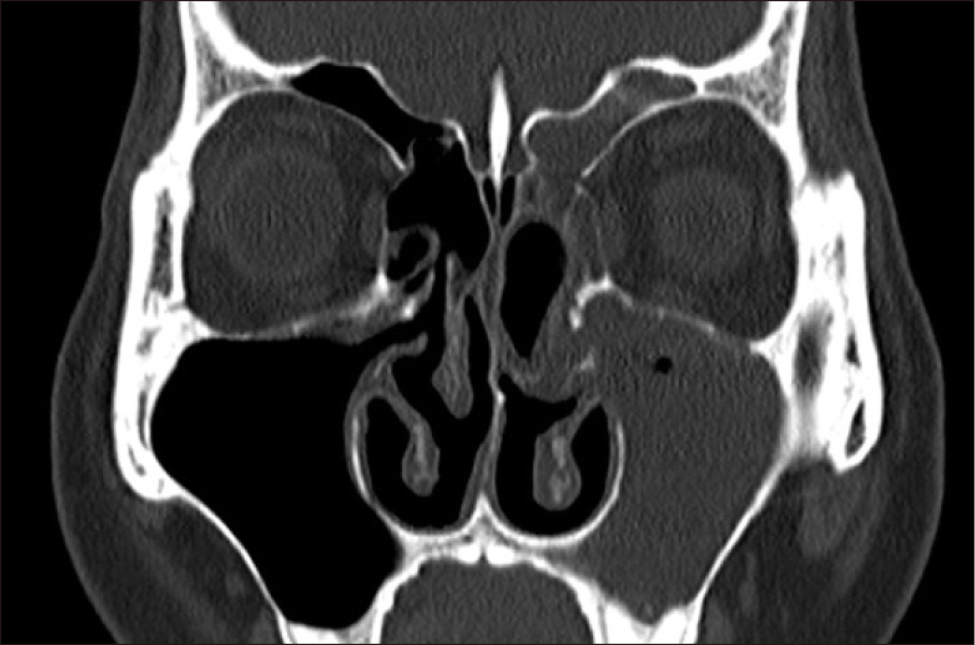

수술 5년 경과 후, 환자는 외래에 내원하였는데 그 동안 병원에서의 코로나 감염 우려로 오지 못했다고 하였다. 환자는 좌측 농성 비루와 후비루 증상이 호전되지 않는다고 하여 당일 CT를 시행하였는데 좌측 상악동에 부분적인 혼탁과 석회화 소견이 보였다(Fig. 3). 외래에서 수 차례 좌측 상악동 세척을 하였는데 환자의 좌측 중비도에서 단단하고 황색을 띠는 솜 형태의 여러 조각들이 관찰되며, 이는 섬세한 섬유성 조직과 얽혀 있었다(Fig. 4). 환자의 중비도에서 발견된 미세한 섬유조직은 수술 당시 사용한 Algi-pack®의 성분과 같은 것으로 생각되었다. 상악동 이물 제거 후 70도 내시경과 Water 영상에서 좌측 상악동에서 특이 소견이 관찰되지 않았다(Fig. 5). 이후 환자는 더 이상의 불편 증상을 호소하지 않았고 재발이나 합병증 없이 외래 추적 관찰 중이다.

jcohns-36-2-54-g3

Fig. 3. Postoperative endoscopic and computed tomography (CT) findings after the surgery. (A) thick, dark yellowish discharge was observed draining from the left maxillary sinus. (B) rod-shaped calcification (arrow) was observed in the left maxillary sinus.

본 증례의 CT 영상에서 관찰된 석회화 소견은 장기간 동안 좌측 상악동에 잔존한 Algi-pack®으로 인한 만성적인 이물 반응 및 염증 과정의 결과일 가능성이 높다.11,12) 칼슘 알지네이트는 갈조류에서 추출한 천연 섬유 조직으로 이루어져 있으며, 상처 부위에서 삼출물을 흡수하여 겔과 같은 물질로 변형되고 동시에 칼슘 이온을 방출하여 알긴산나트륨으로 전환된다. 이 과정에서 방출되는 칼슘 이온은 지혈 과정에 기여한다. 본 증례처럼 흡수성 재료임에도 불구하고 장기간 체내에 잔존하는 경우, 방출된 칼슘 이온이 주변 조직에 침착되거나 염증 반응으로 인해 형성된 섬유성 캡슐 내에서 이차적으로 석회화가 일어날 가능성이 충분하다고 사료된다. 특히 Algi-pack®은 칼슘 알지네이트가 주성분이므로, 이러한 칼슘 성분이 장기간 이물 반응과 함께 체내에 남아있을 때 석회화를 유발할 수 있는 잠재적 요인이 된다. 이는 Algi-pack®의 생체 내 흡수 및 분해 과정에 대한 추가적인 연구가 필요함을 시사하는 중요한 임상적 관찰 결과라고 판단된다.